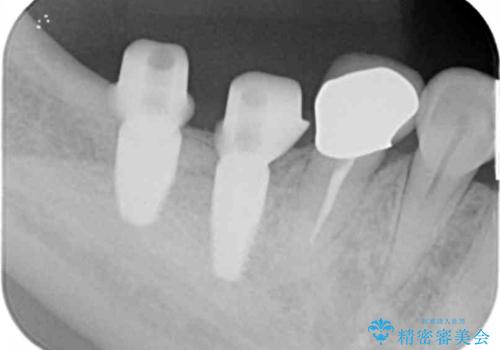

精査した結果、奥歯の根は破折しており抜歯を避けられない状況でした。

咬合力が強く、その他の歯の破折も防ぐために奥歯の咬合機能をインプラントを用いて回復する治療計画を立てます。

- 99万円(インプラント×2・チタンカスタムアバットメント×2・ジルコニアクラウン×2・仮歯×2)費用は治療当時の料金となります

破折した歯はほとんどの場合抜歯が必要になることが多く、インプラントを用いた咬合機能の回復は、また噛めるようになるだけでなく残っているその他の歯を守る意味でも非常に大きな意味を持ちます。